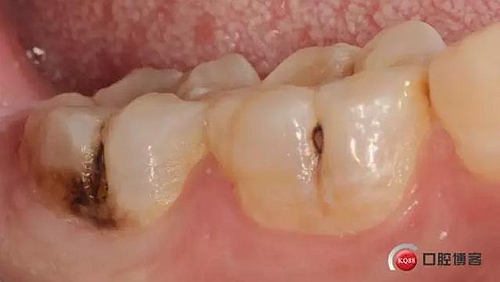

左下后牙樹脂充填一例 科貿(mào)嘉友收錄

這兩顆牙都是單色充填,用的3M家的P60,然后進行了窩溝染色,對于后牙來講很多時候單色就已經(jīng)足夠了,因為畢竟美觀要求不是太高,功能才是最重要的,另外如果真的要用不同顏色的樹脂進行分層的話建議本質(zhì)用飽和度稍高一些的牙本質(zhì)樹脂,這樣堆塑出來的效果能好一些 。